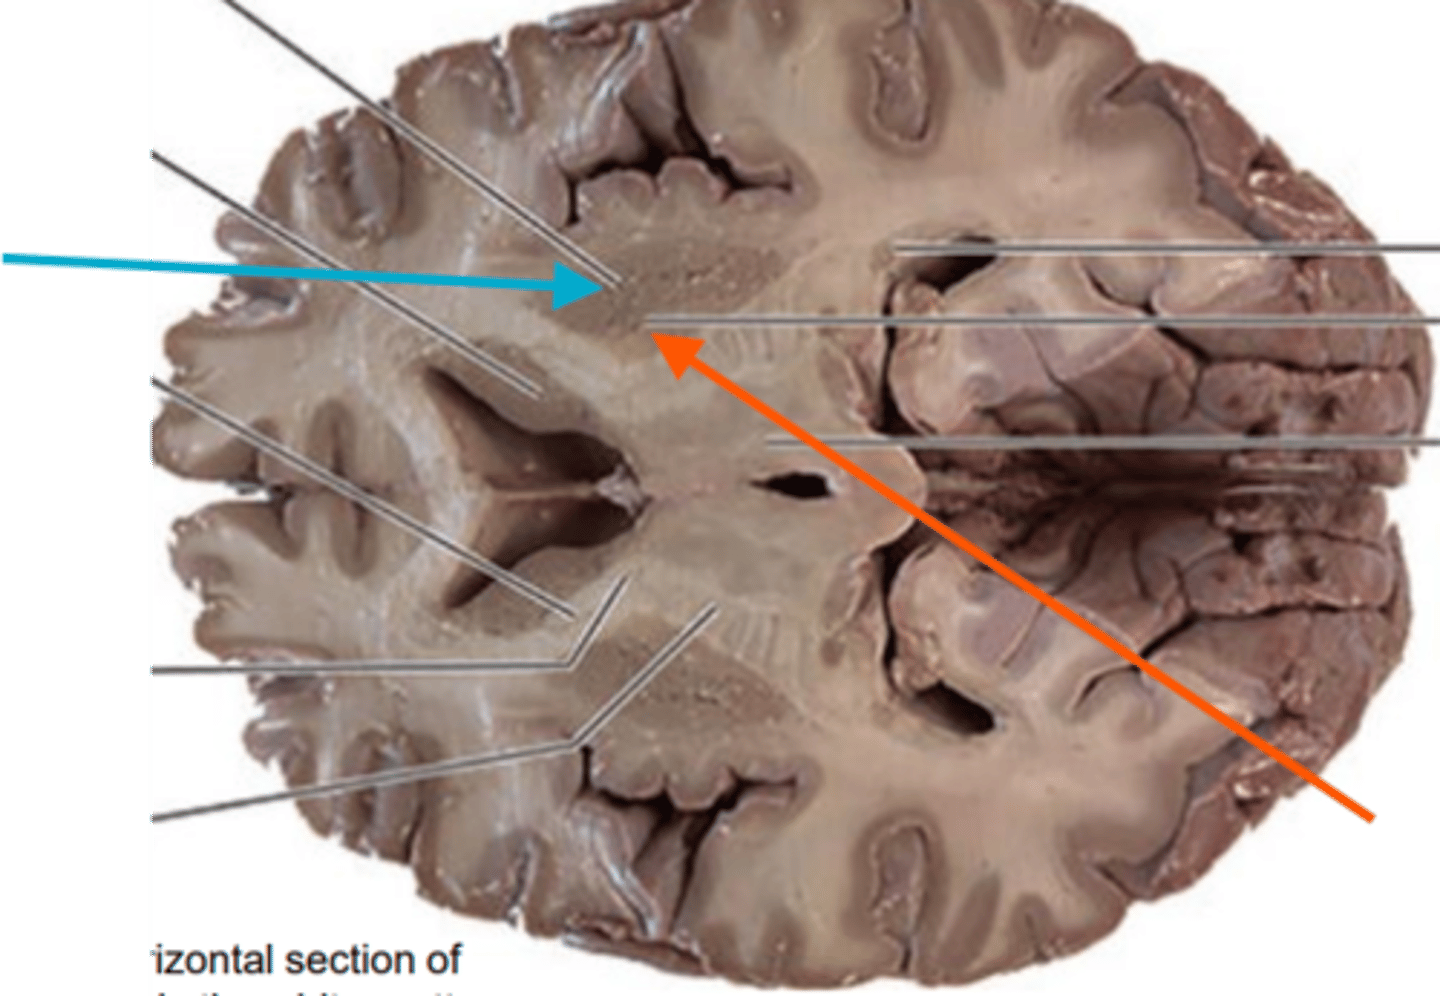

what is the blue arrow pointing to?

blue arrow is pointing to which structure?

The area the blue arrow is pointing to?

structure blue arrows are pointing to?

What area is the blue arrow pointing to?